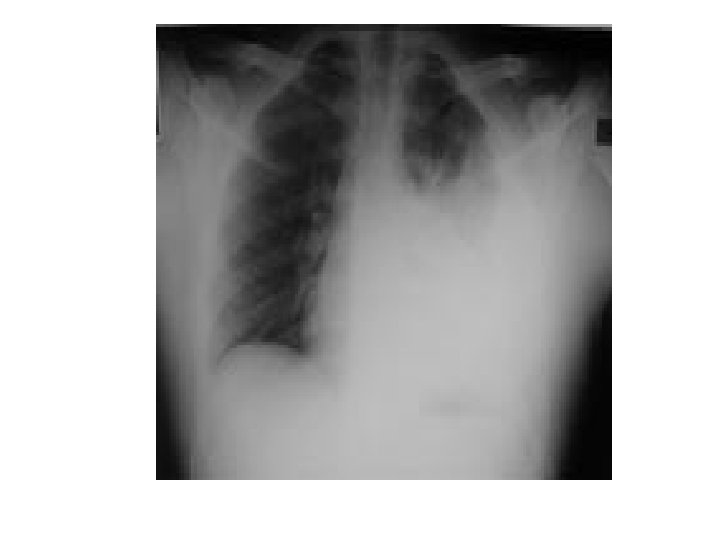

Tumors Left lower zone We say zone not lobe in X-Ray … because we can’t confirm the lobe except by other modality. . E. g. lateral Xray

Left bronchus syndrome , Next slide Plzzz =) Notice , the Trachea is pulled to left side. . WHY ? cuz of fibrosis there is loss of space , loss of ventilation in the left side , the left lung is smaller in size , infective , bronchioectatic , it will pull the trachea toward it.

Left bronchus syndrome : Chronic condition , it is the end sequelae ﺍﻟﻨﺘﻴﺠﺔ ﺍﻟﻨﻬﺎﺋﻴﺔ of lung destruction due to TB In the previous slide , notice the bronchioectatic changes all over the lung ! Rt lung : pt still can breath from it , although it has apical scarring , Rt upper zone infiltration. Lt Lung : has Abcess cavity , Air Fluid levels , cystic bronchiectasis. If we did bronchoscopy , bronchoalveolar lavage , we will see the Fast Bacilli of Mycobacterium TB , which are resistant to 1 st , 2 nd and 3 rd line anti-TB medications ! ﻧﺘﻴﺠﺔ ﺑﺆﺮﺓ ﺍﻟﺘﻬﺎﺑﻴﺔ Left bronchus syndrome : The study was done at KKUH , if u r interested : http: //www. ncbi. nlm. nih. gov/pmc/articles/PMC 462386/pdf/thorax 00339 -0050. pdf 0